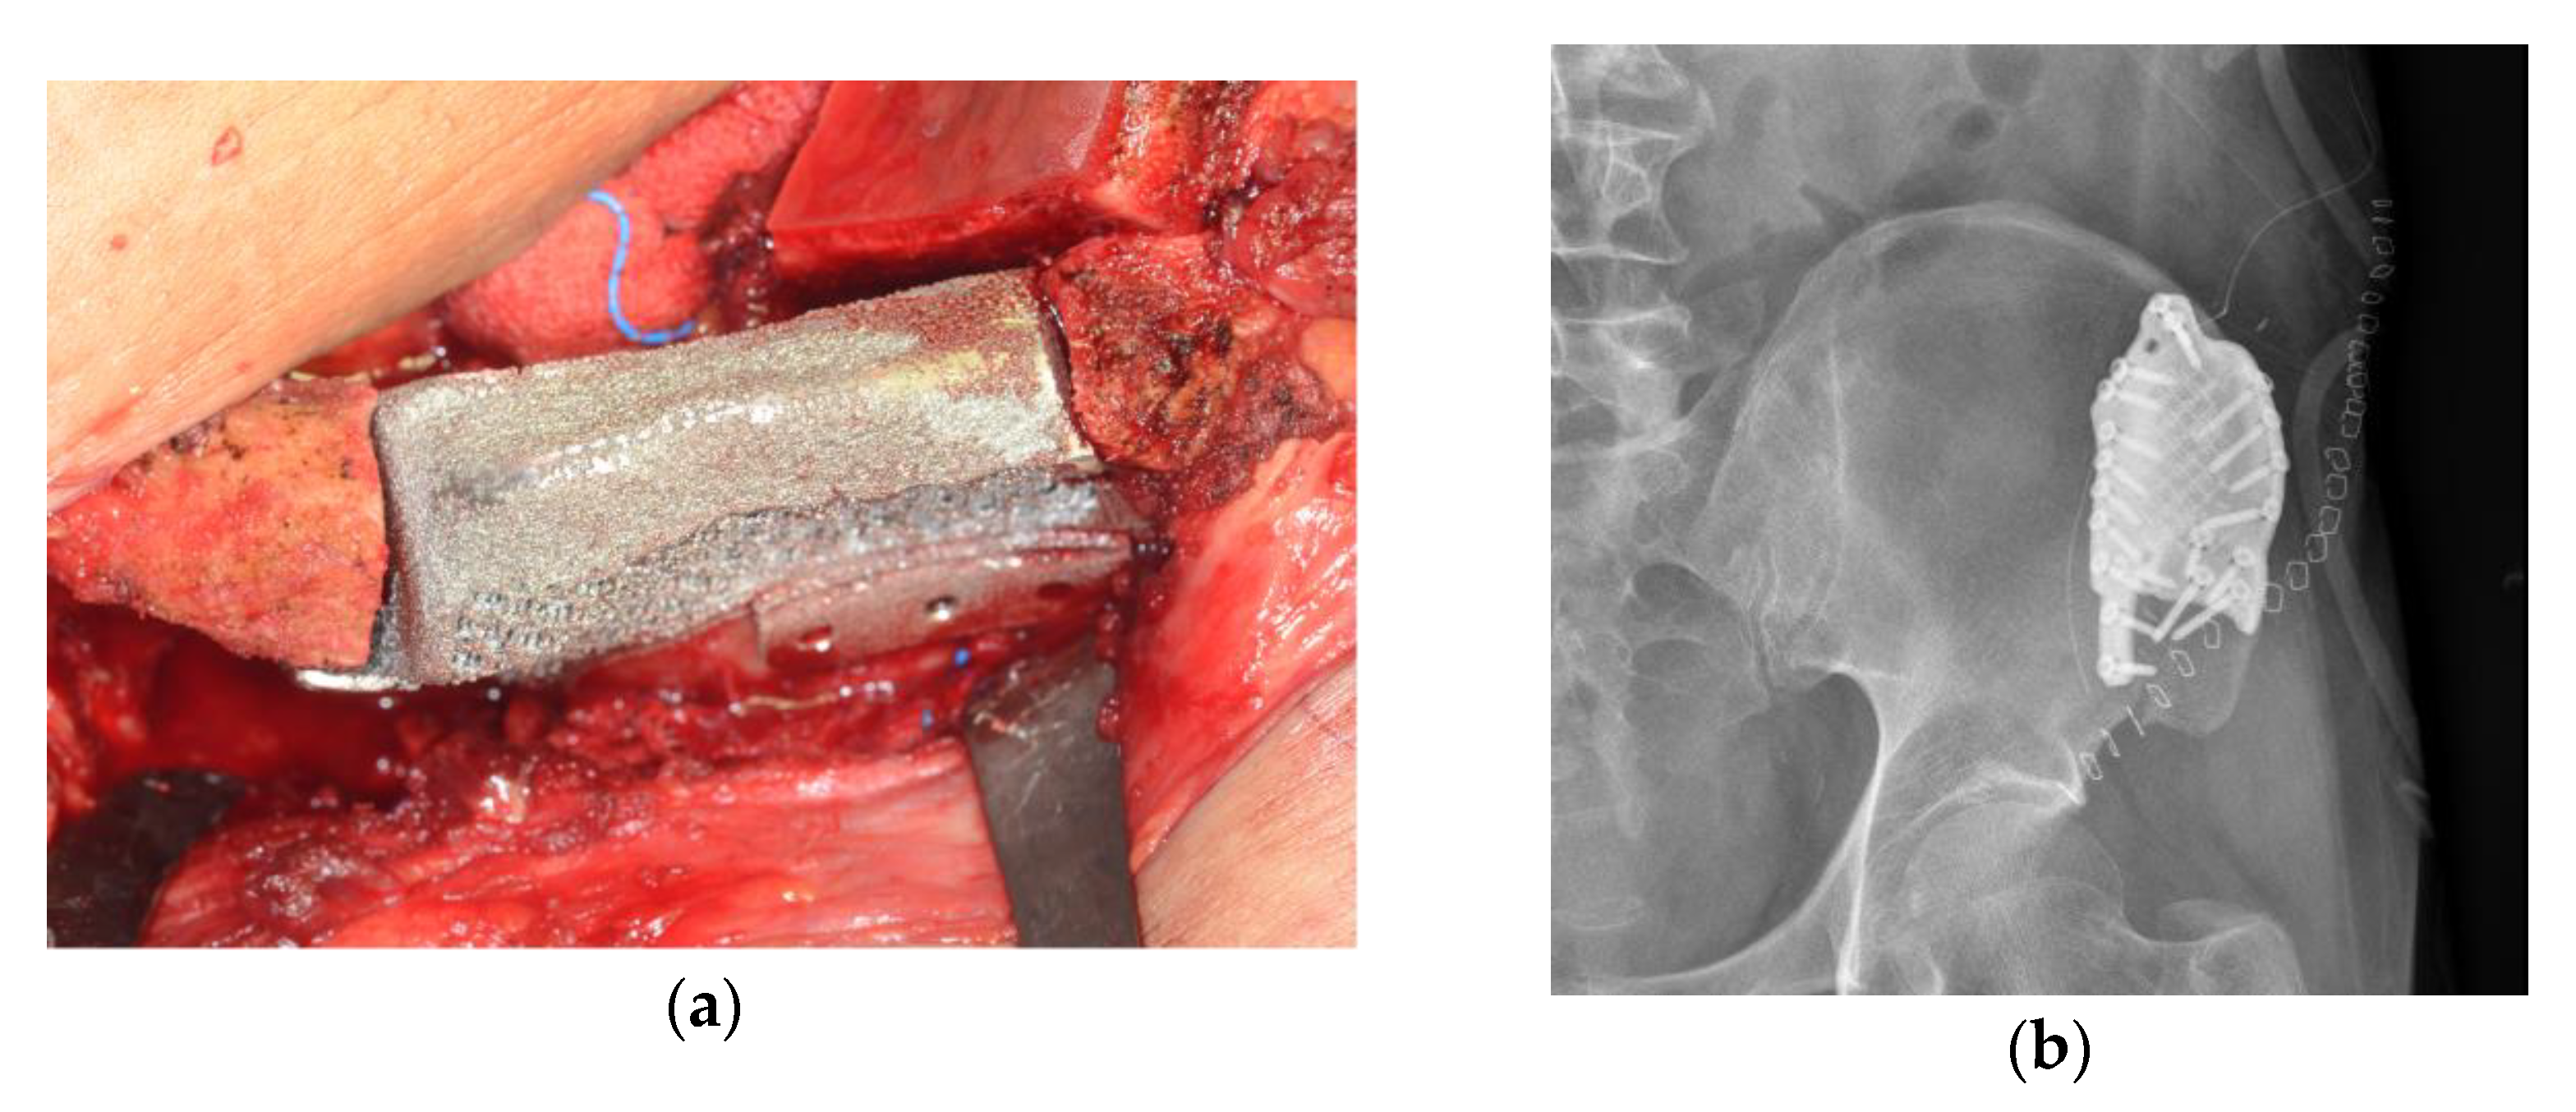

2.1.2. Surgical Technique

2.2.2. Surgical Technique